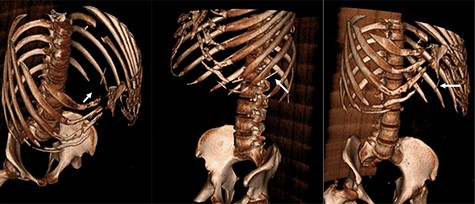

Three-dimensional reconstruction CT scan displaying the foreign body (white arrow) in three different orientations.

This case presented a number of diagnostic uncertainties and management dilemmas. Definite facts ascertained about the foreign body were that it was at least the same density as bone, ~4 cm in length and was not hollow. From this, it was speculated that the object might be a needle, as seen in other cases [3, 4]. There are two manners of foreign body impaction in the spleen, transgastroenteric or transcutaneous [1–5], neither of which appeared feasible here and the lack of any history of foreign body ingestion, psychiatric history nor prior procedures is perplexing. The absence of reactionary inflammation at the time of presentation implicates its presence in the spleen for a protracted, perhaps since childhood. Haematoma occurrence after the VATS procedure may indicate that perioperative seeding was responsible for the foreign body colonization.